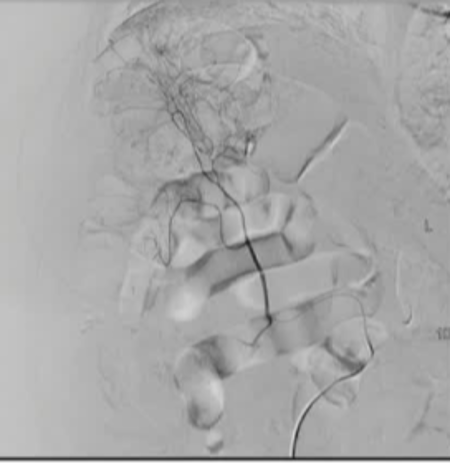

Empiric Embo of Tumor Related GI Bleed

|

Rectal CA |

Met to duodenum |

-

37 angios in 26 patients

Most had findings of tumor

Neo or hyper-vascularity

91% for acute bleeding

50% for chronic bleeding

No ischemic complications

Tandberg - 2012 JVIR 23:1445